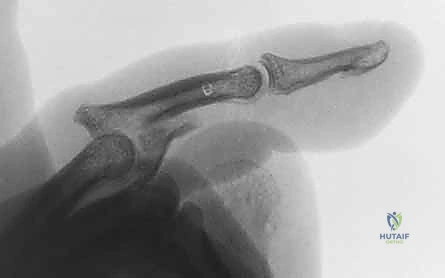

3. التثبيت الخارجي الديناميكي (Dynamic External Fixation)

تعتبر هذه التقنية ثورة في علاج الكسور المفتتة بشدة (كسور بيلون) حيث يكون العظم مهشماً كعجلة القيادة المكسورة.

* كيف تعمل؟ بدلاً من فتح المفصل، يقوم الدكتور هطيف بإدخال أسلاك معدنية دقيقة عبر الجلد إلى العظام السليمة فوق وتحت المفصل المصاب. يتم توصيل هذه الأسلاك بإطار خارجي مرن (مثل إطار سوزوكي Suzuki Frame).

* الميزة: يعتمد هذا الإطار على مبدأ "الشد الرباطي" (Ligamentotaxis). فهو يسحب المفصل بعيداً عن بعضه، مما يسمح للقطع العظمية المفتتة بالاصطفاف في مكانها الطبيعي بفضل الشد المعاكس للأربطة المحيطة، وفي نفس الوقت يسمح للمريض بثني ومد